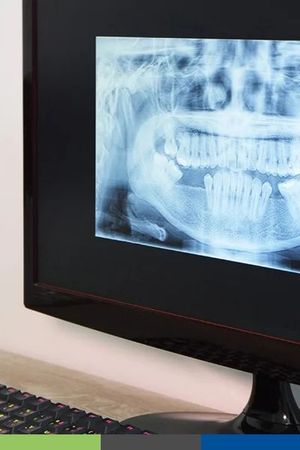

Digital X-Rays

Digital x-rays are safe, quick, and comfortable. Using the latest technology, we can create crisp, high-resolution images of your mouth’s structure, so we can make accurate diagnoses and treatment plans. Digital x-rays use only a fraction of the radiation as traditional film x-rays, so you can rest easy. Most patients receive one or two full sets of x-rays every year, but we may recommend additional imaging in the case of a dental emergency, or if we find an oral health issue that we need to investigate further.